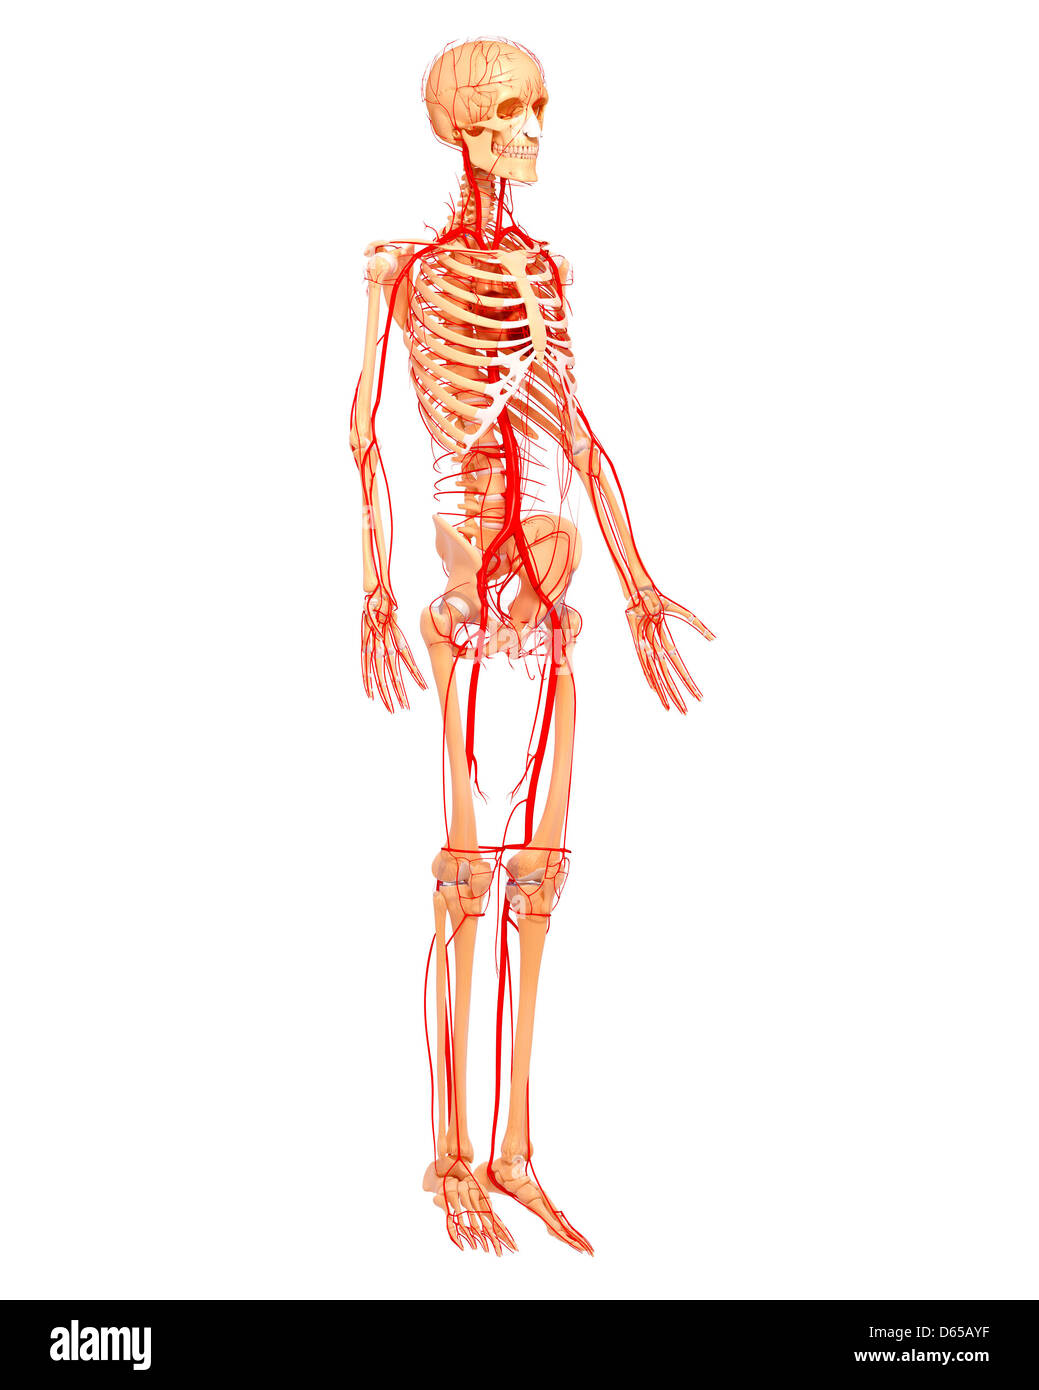

Système cardiovasculaire, artwork Banque D'Imageshttps://www.alamyimages.fr/image-license-details/?v=1https://www.alamyimages.fr/photo-image-systeme-cardiovasculaire-artwork-55415491.html

Système cardiovasculaire, artwork Banque D'Imageshttps://www.alamyimages.fr/image-license-details/?v=1https://www.alamyimages.fr/photo-image-systeme-cardiovasculaire-artwork-55415491.htmlRFD64B0K–Système cardiovasculaire, artwork